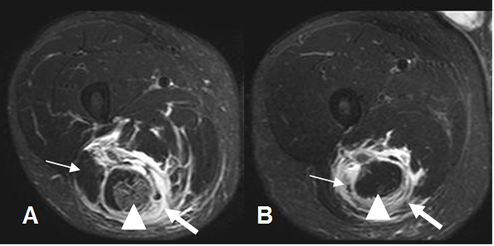

Fig 25 A. Ruptura muscular.

A: RM axial en STIR. Igual paciente anterior. Músculo biceps femoral normal. (Flecha delgada). Hay algunas fibras hiperintensas en el músculo semitendinoso, sin ruptura de fibras, por lesión grado 1. (Punta de flecha). No se identifica el músculo semimembranoso, por ruptura retraída. (Flecha gruesa).

B: RM axial en STIR. Músculo semitendinoso normal. (Punta de flecha). No se identifican los músculos biceps femoral (Flecha delgada), ni semimembranoso (Flecha gruesa), por rupturas retraídas.

Fig 25 B. Ruptura muscular.